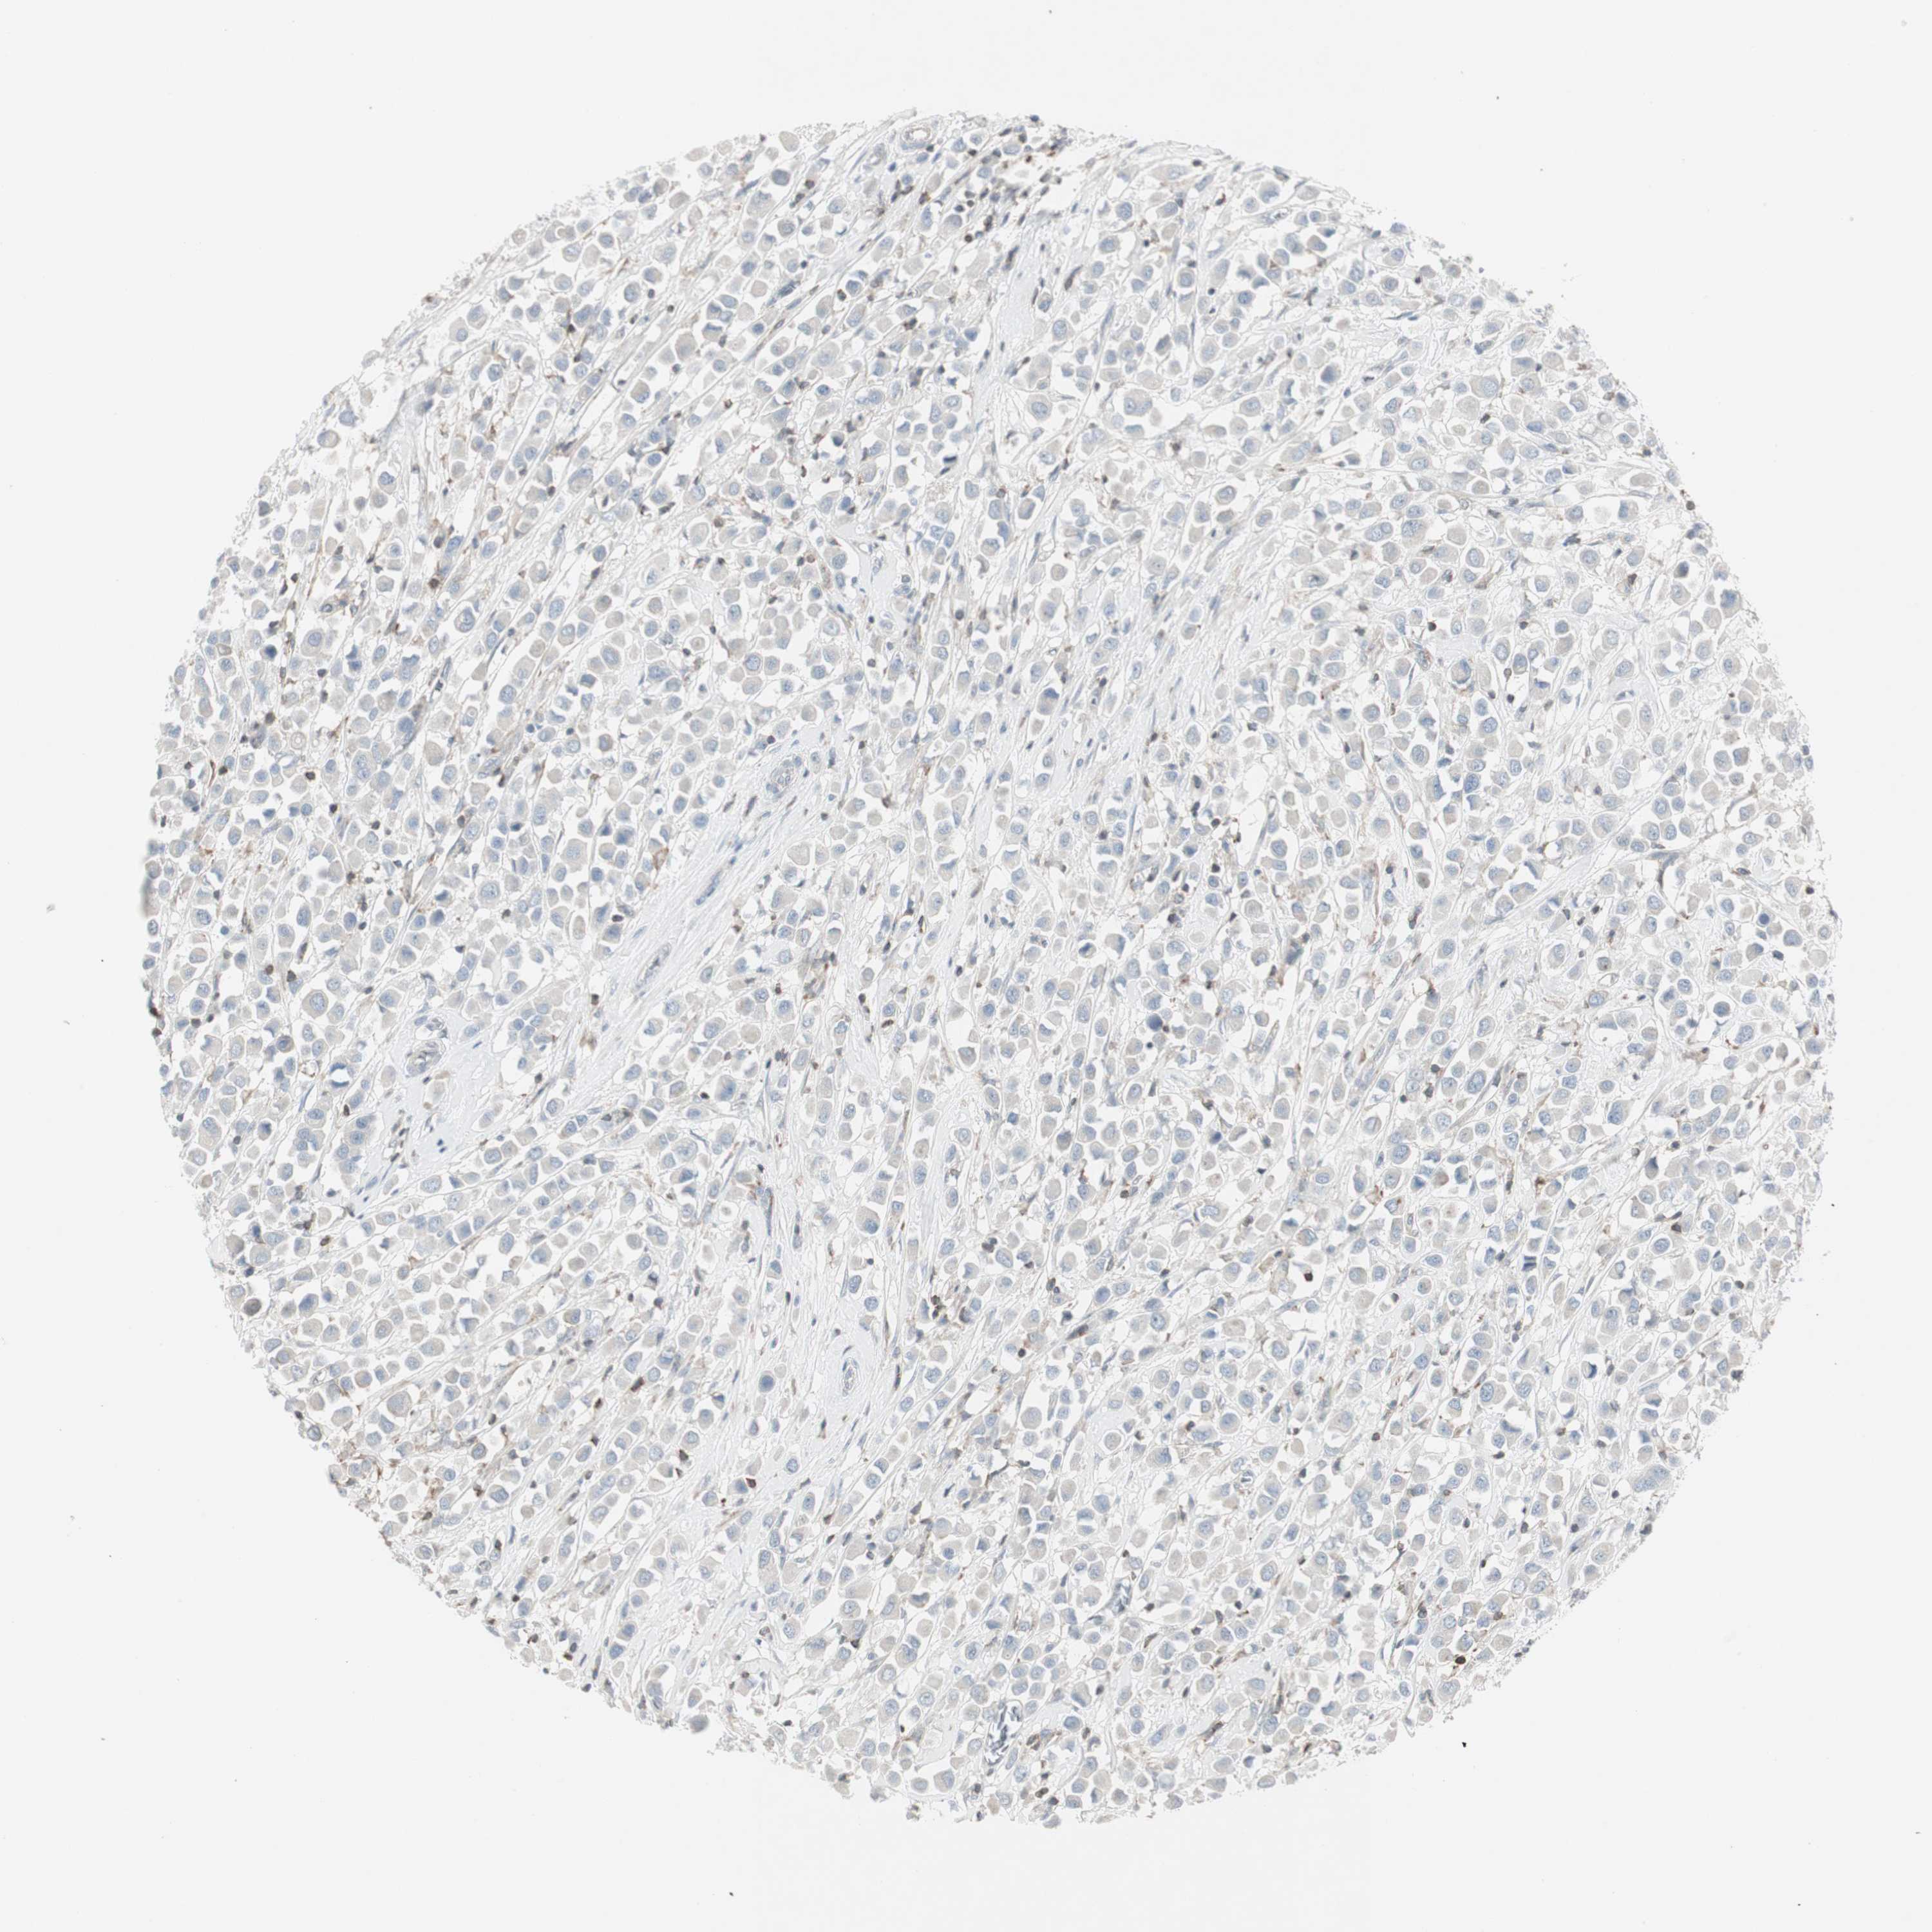

CANCER BREAST CANCER Show tissue menu

BRCA TCGA BRCA VALIDATION PROTEIN EXPRESSION